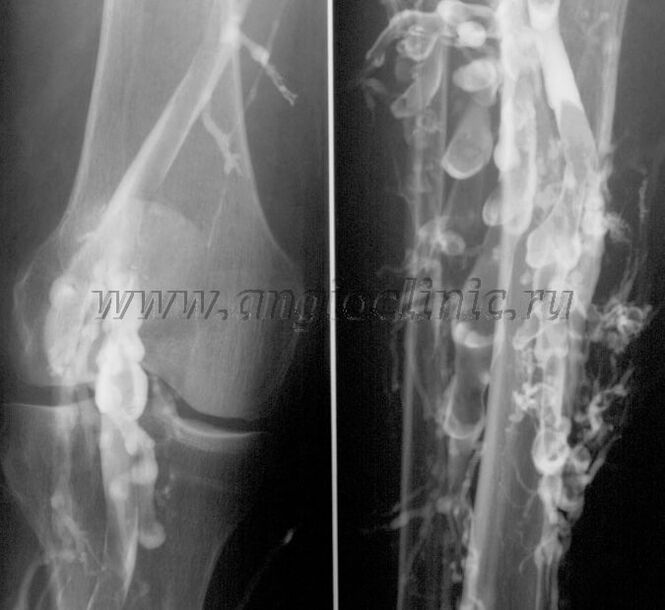

Kontrastinė venografija

Paprastai pilnai venų patologijai diagnozuoti pakanka ultragarsinio skenavimo, tačiau kai kuriais atvejais būtina ištirti giliųjų ir paviršinių venų sistemos būklės ryšį, ypač esant venų varikozės atkryčiams ir antrinei venų varikozei.

Šioms problemoms spręsti naudojamas kontrastinis rentgeno tyrimas. Punkcuojamos juosmens venos ir skiriamas kontrastas. Rentgeno aparato monitoriuje stebimas kontrasto judėjimas, atliekami visi reikalingi bandymai ir projekcijos. Šiuo metu venografija venų varikozei gydyti naudojama labai retai.